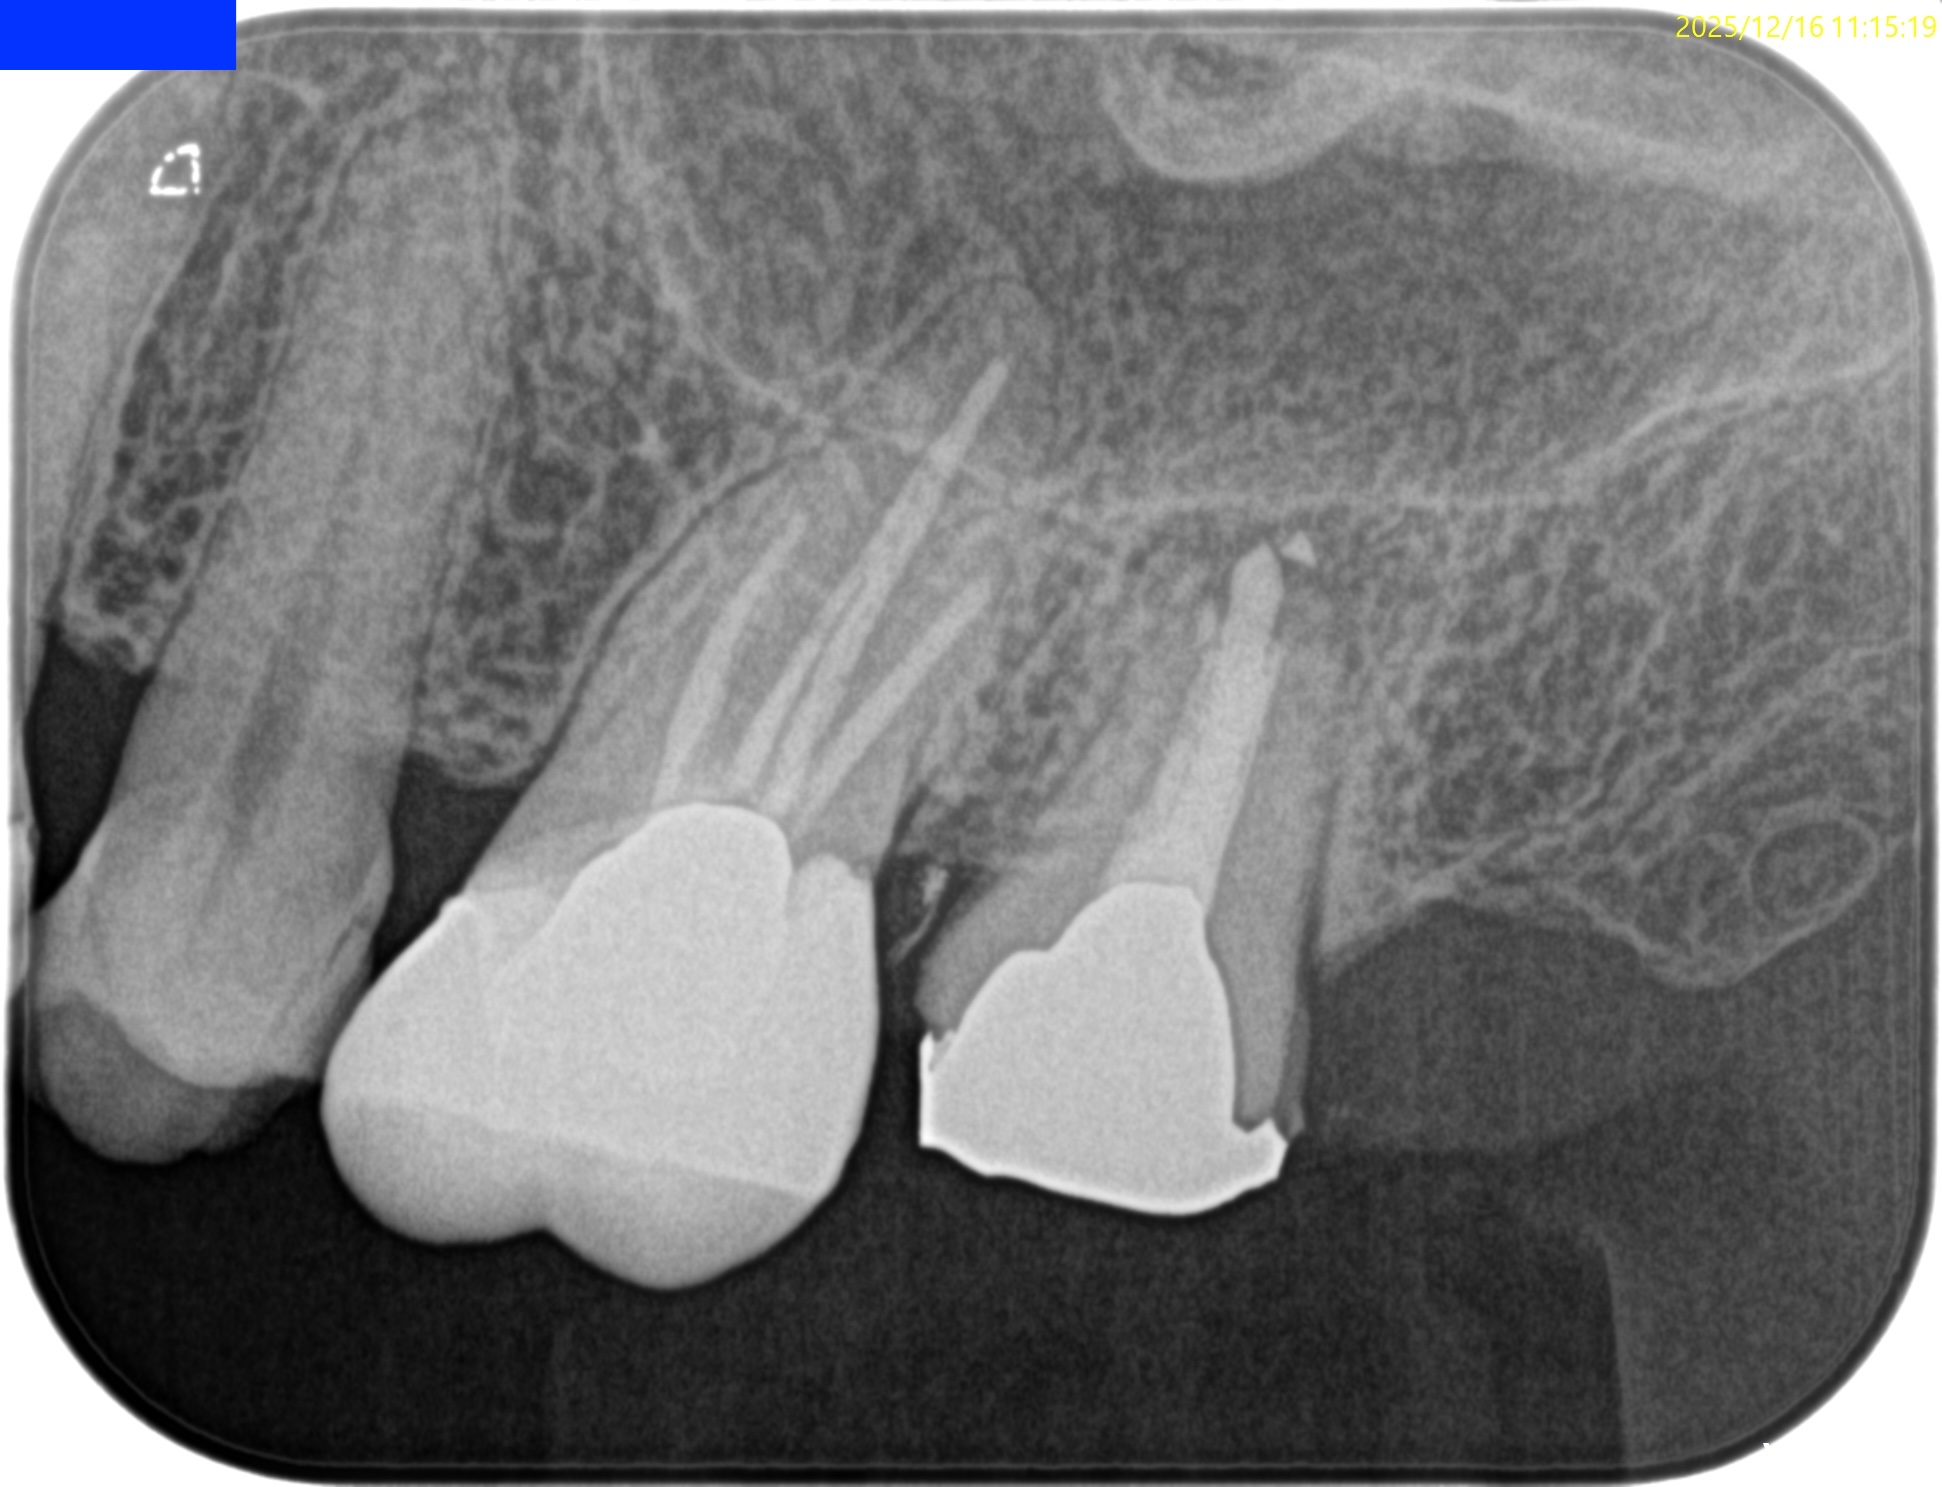

Pre-op Endo test(2025.12.16)

Pulp Dx: Previously treated

Periapical Dx: Symptomatic apical periodontitis

Recommended Tx: Intentional Replantation⇨Core build up